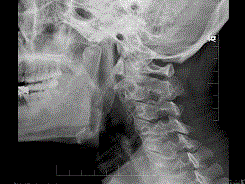

37岁,女性患者,咽部异物感、咽痛伴反射性耳痛、头颈部不适近一年余,X线检查如图所示,请选择正确的描述和答案 ( ) A、右侧茎突过长综合征...

问题 37岁,女性患者,咽部异物感、咽痛伴反射性耳痛、头颈部不适近一年余,X线检查如图所示,请选择正确的描述和答案 ( )

选项 A、右侧茎突过长综合征 B、正常茎突 C、右侧茎突长约4.0cm D、双侧茎突过长综合征 E、左侧茎突长约3.5cm

答案 CDE